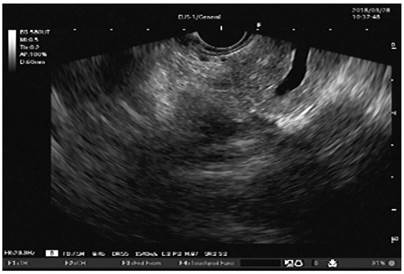

Dilation of the Wirsung duct and enhancement of its walls (Figure 4)

Figure 4 Fujinon’s linear EUS. Wirsung duct dilation in the body of the pancreas and enhancement of its walls (image courtesy of the Union of Surgeons SAS, Lázaro Arango).